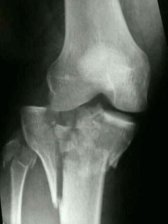

These fractures can be extremely challenging to deal with. Often times there is some degree of bone loss, or empty spaces ("voids") where pieces would notmally occupy. The x-ray at right shows a badly comminuted tibialplateau fracture the is also an "intra-articular" (involving the joint itself, see below)injury because of the significant disruption of the joint surfaces.

Restoring joint surfaces as best as possible is critical in these injuries, as is restoring more normal alignment and position of the bone.

"Intra-Articular"

Intra-articular fractures are those injuries that involve and extend into the actual joint compartment(s) causing injury, and sometimes deformity, to the joint cartilage surfaces.

The same can be said for intra-articular fractures. Best case scenarios show that even though many joint surface injuries can be restored to very good condition, they're never perfect, and never return to "pre-injury" normal states.